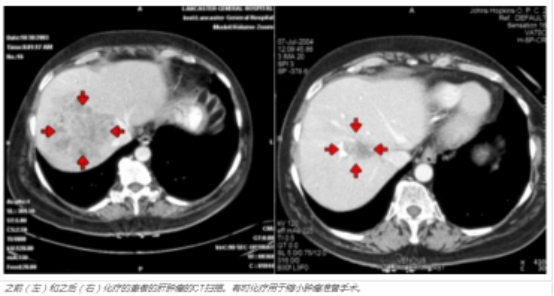

在某些情况下,可能看起来这种疾病涉及您的肝脏的大部分,并且可能确定手术是不可能的。然而,在我们的中心,有时 在手术前结合化疗来缩小肿瘤和门静脉栓塞以帮助肝脏“生长”,我们的外科医生能够去除肝脏中的所有癌症。

我们的多学科方法涉及医学和外科肿瘤学家密切合作。我们经常使用化疗来准备其他机构可能不会考虑手术的患者,以便他们成为约翰霍普金斯医学院的手术候选人。